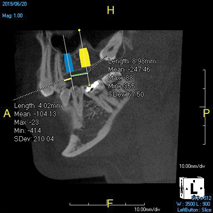

(7.) Treatment planning an implant case is made easier and more accurate by virtually placing implants of the chosen length and diameter and measuring the desired mesiodistal spacing prior to surgery.

Figure 7

The use of CBCT has been shown to reduce the rate of implant failures.8 Placing a root-form implant into an asymmetrical section of bone can be done more accurately and safely if the location is visualized in 3D prior to placement. The primary advantage of a cross-sectional or coronal view of the bone is that it shows the shape of the anatomy, and any measurements taken from a CBCT image are accurate to 0.1 mm. The placement of an implant to replace a single tooth is far easier to accomplish when the adjacent roots and other important nearby structures, such as the inferior alveolar nerve and the sinus, are identified and measured relative to the desired position of the implant. In addition, CBCT enables an implant to be virtually placed prior to the actual surgery.16 The need for an accurate digital map only increases if a case involves multiple implants or is otherwise more complex (Figure 7). Regardless of the complexity, many clinicians who place implants advocate for the use of surgical guides to aid in precise positioning. This is another important use of CBCT in implant dentistry. Accurate surgical guide fabrication requires a clear and accurate CBCT digital imaging and communications in medicine (DICOM) file to be sent to the party constructing the guide.17